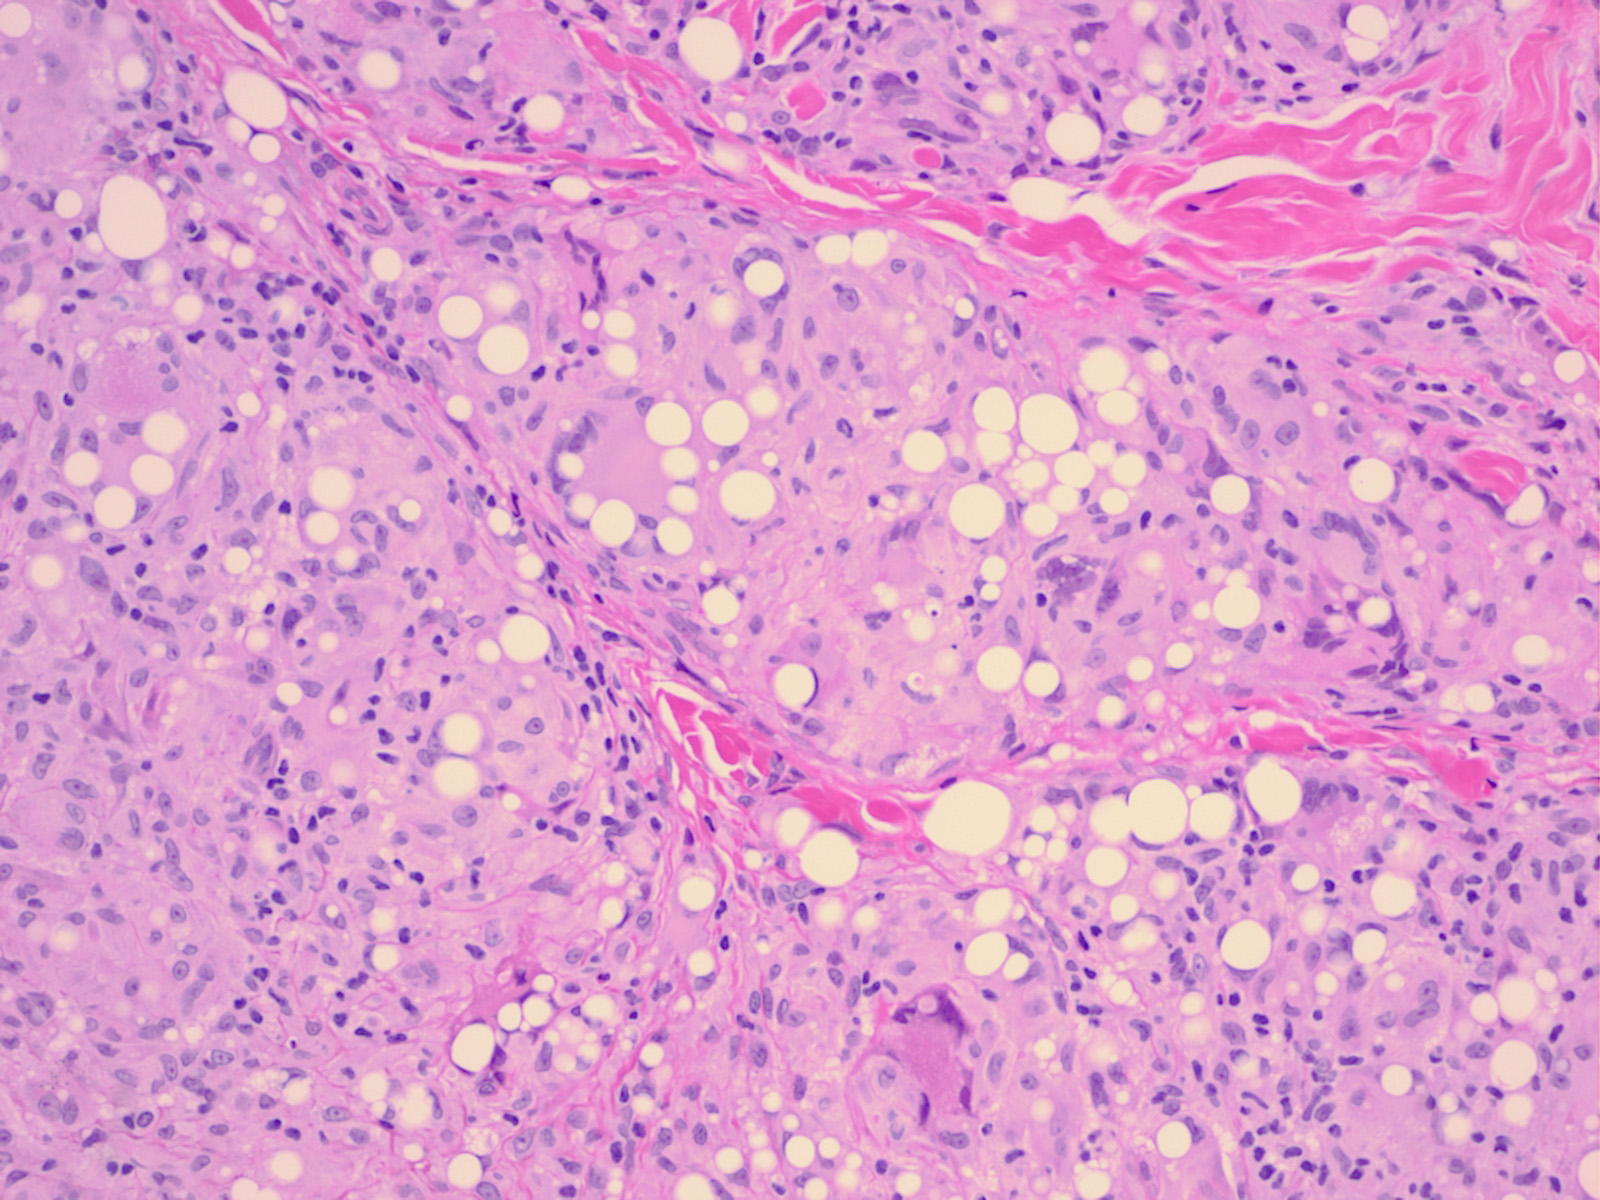

Paraffinomas have a “Swiss cheese” appearance because of the presence of numerous ovoid or round cavities that show great variation in size. These cavities represent spaces occupied by the oily substance . The spaces between the cavities are taken up in part by fibrotic connective tissue and in part by an infiltrate of macrophages and lymphocytes. Some of the macrophages have the appearance of foam cells. Variable numbers of multinucleated foreign-body giant cells are present.